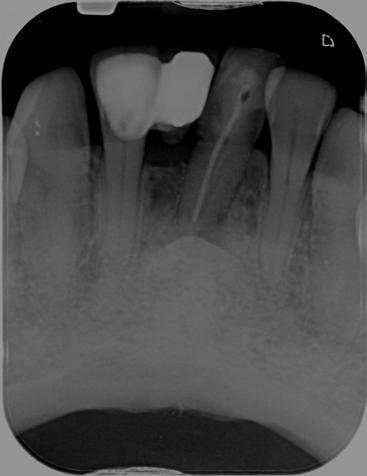

A 37-year-old female (Mrs H. K.) was referred for endodontic assessment and management of teeth 16, 26 and 46 before orthodontic space management. Clinical and radiographic evaluation, including CBCT scanning, revealed that teeth 16

and 26 were asymptomatic clinically; however, imaging confirmed the presence of missed mesiopalatal root canals, short obturation lengths in other canals, and distinct periapical radiolucencies. Both maxillary molars were diagnosed as previously root-filled with inadequate quality, exhibiting infected rootcanal systems (RCS), chronic apical periodontitis, and external apical inflammatory resorption associated with restoration breakdown, cracks, and recurrent decay. Tooth 46 shared similar diagnostic features but also demonstrated concurrent periodontal involvement, indicating a combined endodontic–periodontal lesion.

Figure 1: CBCT sagittal section demonstrating periodontal bone loss involving the furcation area of tooth 46.

Figure 2: CBCT transverse section demonstrating bone loss involving the furcation area of tooth 46.